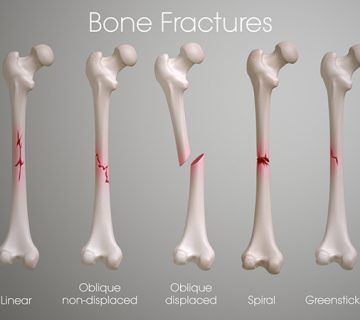

Surgery to correct axial deviations of the knee

Surgery may be recommended in some cases to correct axial deviations of the knee. But the final decision to perform surgery should be made by an orthopedic specialist based on your diagnosis and conditions. Surgery may be suggested in cases where knee function is affected and strengthening exercises and physical therapy do not yield the desired result.

The type of surgery required to correct axial deviations of the knee varies depending on the cause of the problem and its severity. Surgery usually involves one of the following procedures:

1. Joint replacement: In this method, the surgeon cuts a part of the knee bone and replaces it by using screws and metal plates to place the knee joint in the right place. This method is usually used to correct axial deviations of the knee.

2. Cartilage repair: In some cases, surgery may include cartilage repair. This surgery may involve cutting or repairing the cartilage of the knee to return the knee axis to normal.